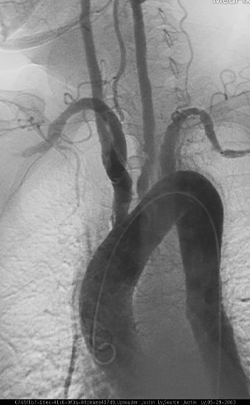

- Se solicita una angiografía y se observa lo siguiente:

La angiografía ha sido considerada como estándar de oro para el diagnóstico de enfermedades vasculares que producen anormalidades del lumen; sin embargo, se sugiere el uso de la resonancia magnética para visualizar etapas tempranas de la enfermedad con alta precisión y debe ser considerado uno de los métodos de imagen de elección para el diagnóstico de arteritis de Takayasu.2